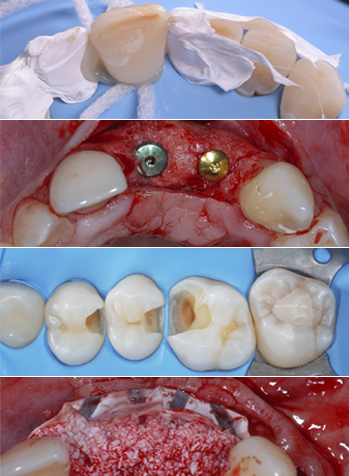

Dr. Ramón Gómez Meda

El Dr. Gomez Meda nos explicará los Trucos y Consejos para obtener la Excelencia en la Regeneración Ósea Guiada Horizontal y Vertical